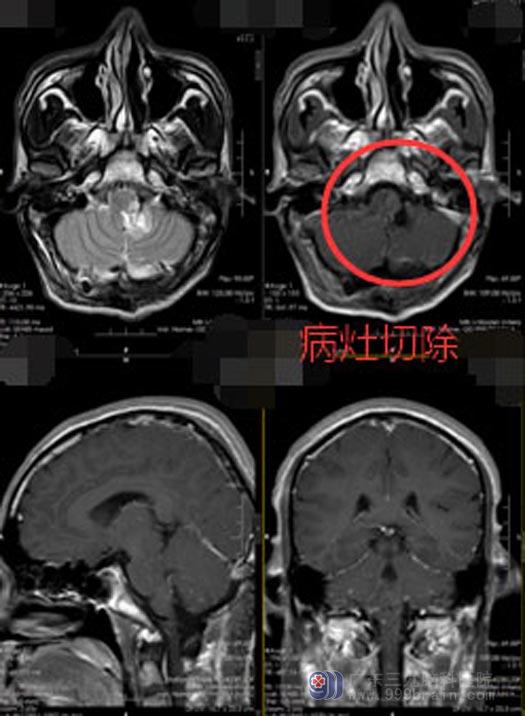

患者及家属知情同意后,由鲁明主刀在全麻下行“延髓、脑桥左侧-左侧小脑上角病变切除术”,后颅窝导航定位,取后正中切口,术中导航再次定位,切除左侧小脑上角及左侧延髓-脑桥病变组织,术区无出血,手术顺利。

术后,许先生生命体征稳定,头晕感觉消失,左侧面部麻木感基本缓解,左侧肢体深感觉恢复正常,四肢活动好。术后一周已可以下床自主活动了。他开玩笑地说:一直以为是颈椎病引起的头晕,看来是冤枉它了。